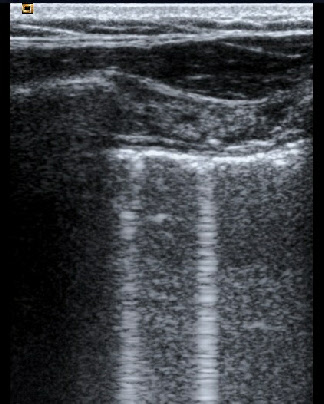

Celle d’une coupe longitudinale montrant un syndrome alvéolaire a minima avec, en arrière d’une couche superficielle d’alvéologrammes hydriques à peine visibles, la présence d’alvéologrammes hydro-aériques sous la forme d’impuretés postérieures (rings downs nombreux et plus marqués que les rings downs habituels du poumon normal) formant une “ trop belle image postérieure ” générée à partir d’une surface pulmonaire parfaitement mobile.

Coupe longitudinale présentant un syndrome alvéolaire a minima. Juste en arrière de très minces alvéologrammes hydriques en superficie, mise en évidence d’alvéologrammes hydro-aériques reconnaissables aux impuretés postérieures en queue de comète (formant de “ trop belles images ” artéfactielles).